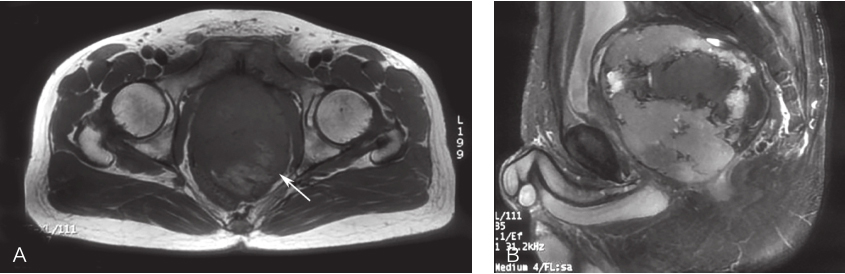

患者,男性,38岁,2017年3月因“体检发现盆腔肿物2周”就诊。完善盆腔MRI(图1)、经直肠超声等检查,考虑盆腔内间叶源性肿瘤伴出血。PET-CT示:盆腔膀胱、直肠间见一软组织肿块,大小约9.4cm×12.2cm×11.5cm,代谢活跃,倾向恶性病变。经直肠肿物穿刺活检病理示:梭形细胞肿瘤,免疫组织化学染色提示胃肠间质瘤:CD117(+),CD34(+),DOG-1(+),Desmin(-),S-100(-),SMA(-),Ki-67(Li:5%)。 穿 刺组织基因检测:c-KIT基因9外显子点突变(c.1509-1510insGCCTAT.)。术前评估为可切除性直肠GIST,但考虑到肿物较大且与周围组织器官关系密切,直接切除有联合脏器切除可能,且难以保留肛门功能,遂决定行术前靶向药物治疗。

图1 首诊盆腔MRI表现

A.横断面;B.矢状面

2017年3月盆腔MRI示:盆底直肠膀胱间隙见T2较高T1较低信号软组织影,直径约10cm,病变内部信号不均匀,见多发不规则大片状T1较高T2等信号区,并见气-液平面,考虑间叶组织源性肿瘤伴瘤内出血;DWI序列环周呈高信号,中心大片呈低信号区;病灶推挤膀胱、前列腺及精囊向前上方移位,推挤直肠向后移位,大部分边界清。